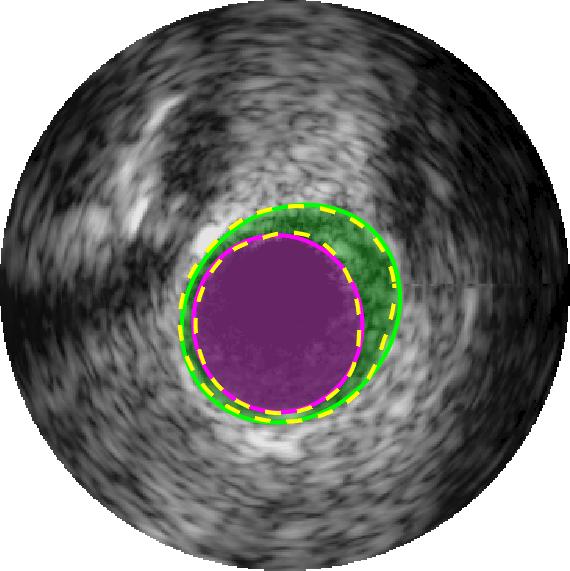

Qualitative evaluations are illustrated in Figure 4 and show the successful segmentation results of the proposed EREL selection strategy for 20 IVUS frames. The lumen areas are highlighted by the magenta colour while the media regions are green. Also, the manually annotated contours for both lumen and media are drawn as yellow dashed lines. As we can see, the chosen frames contain a variety of lumen and media morphologies.